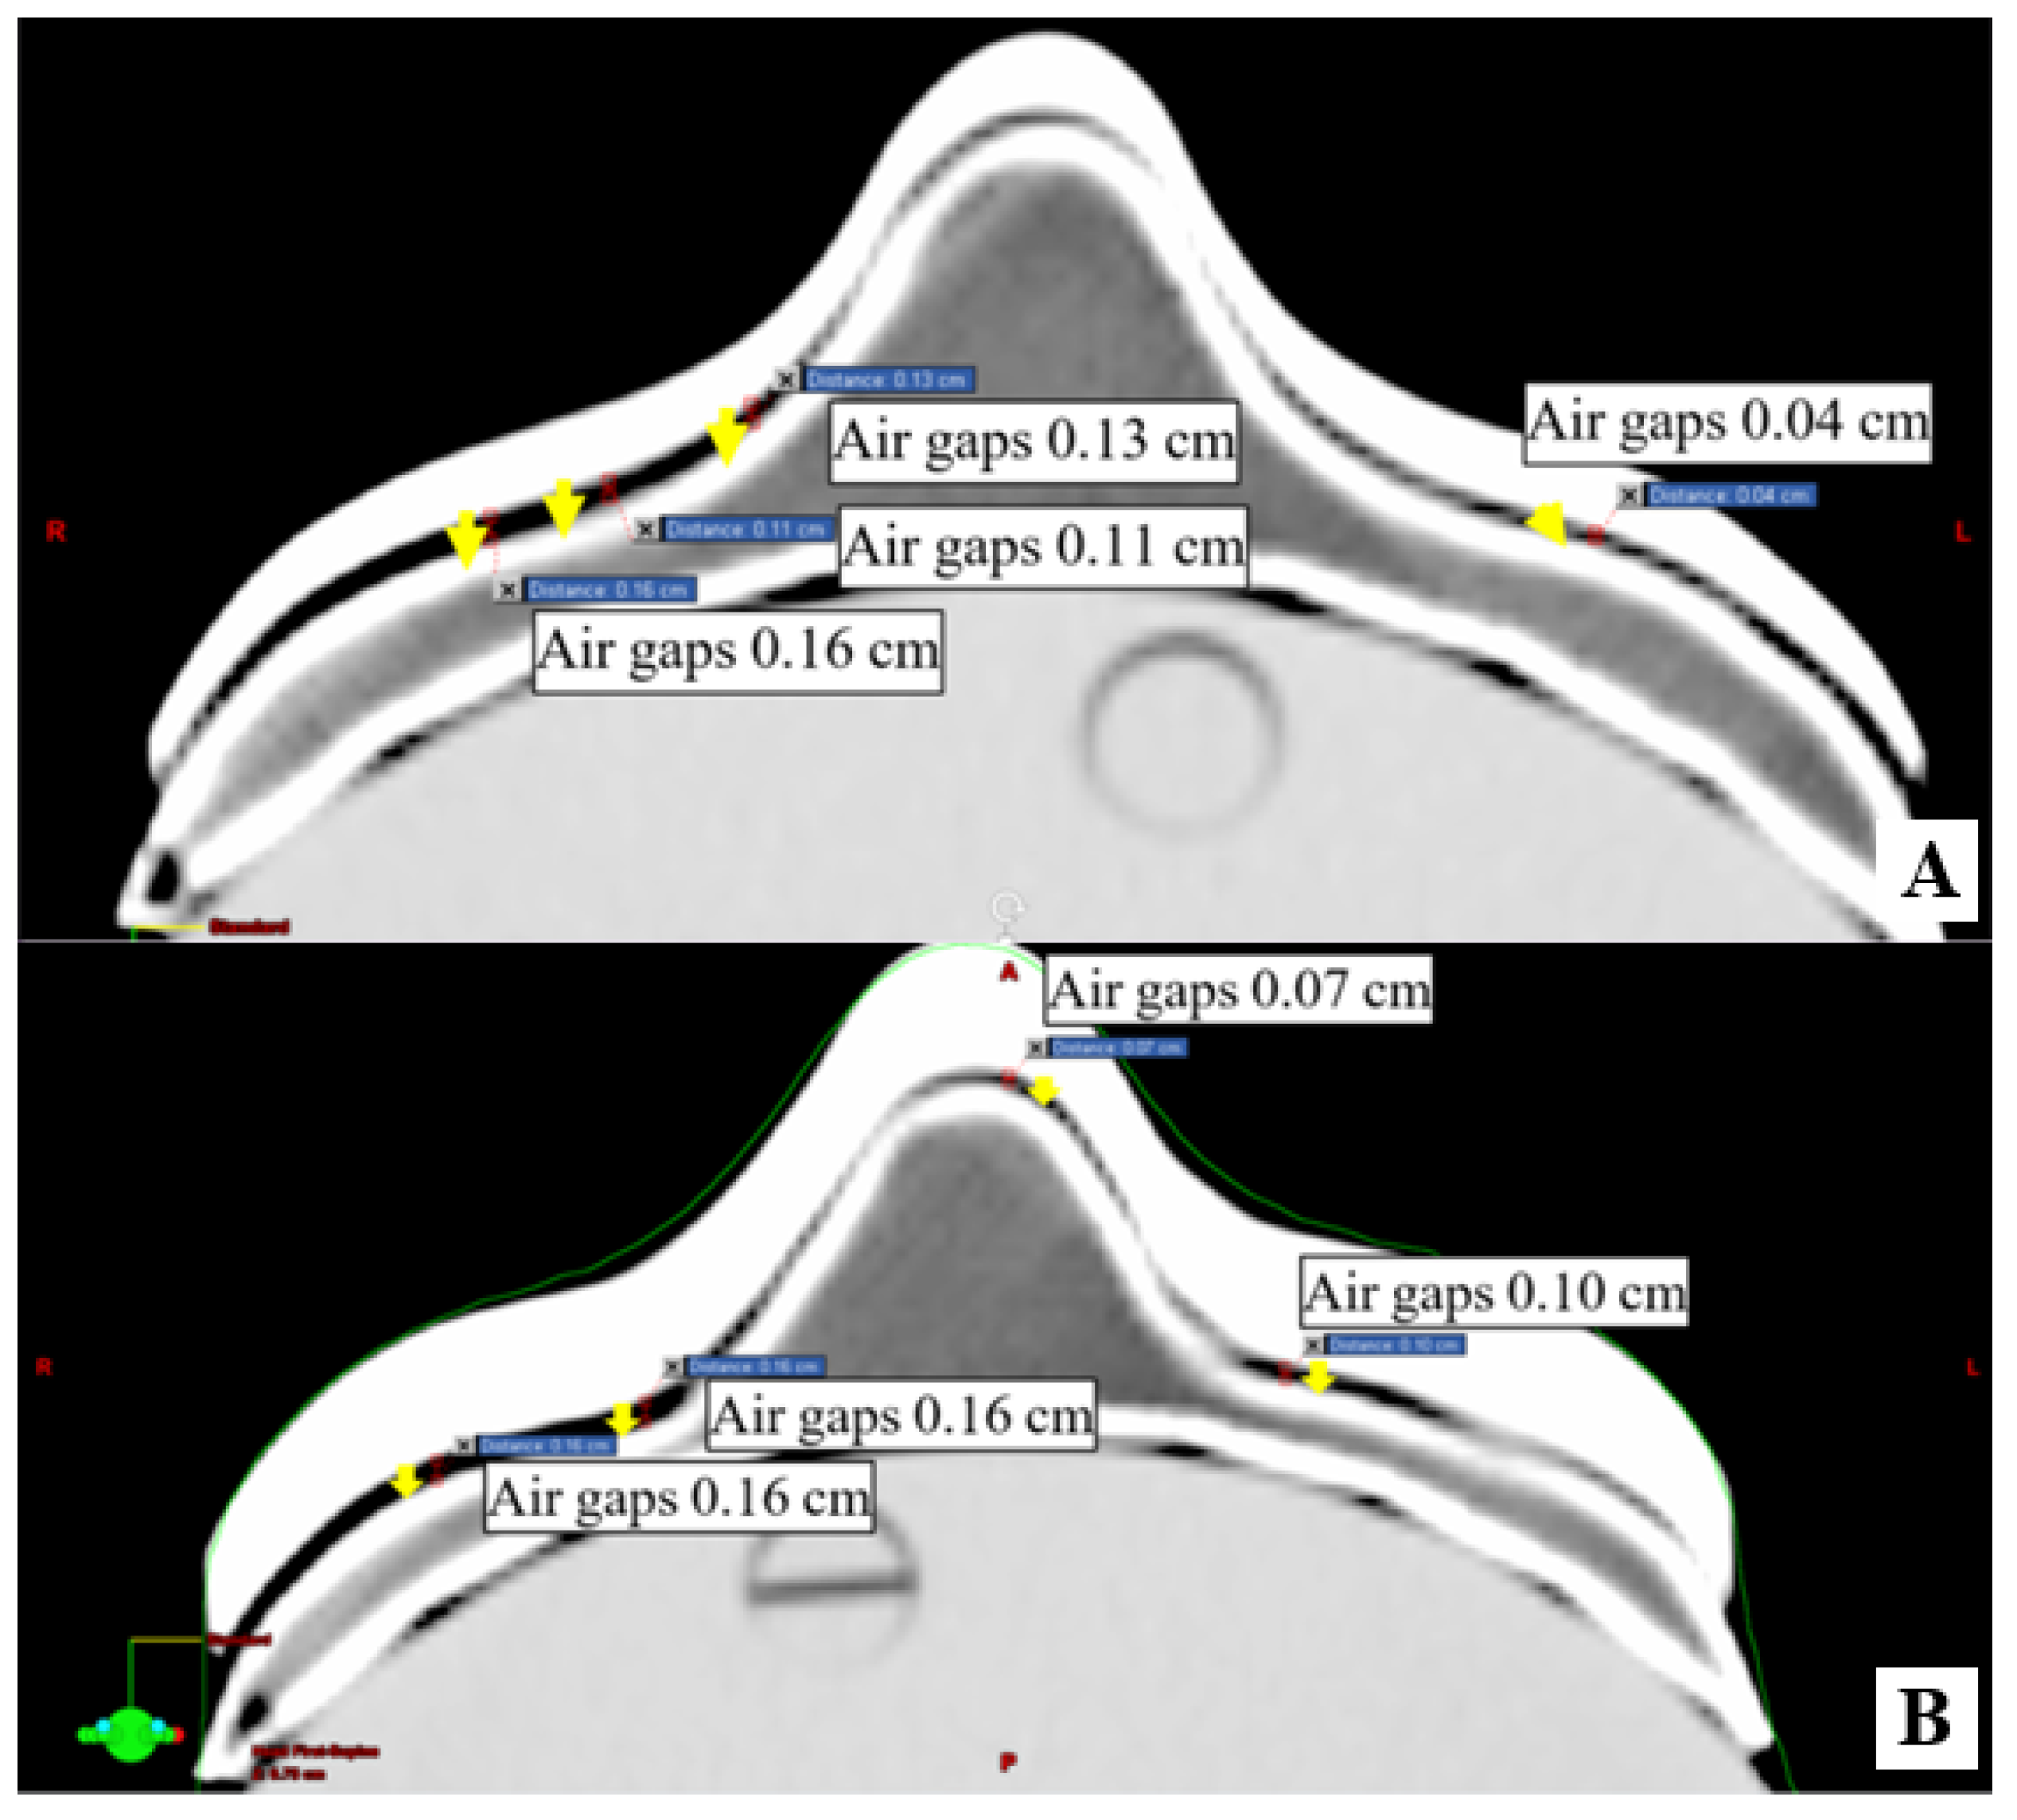

2.3. Conformity of 3D-Printed Boluses

3.2. Conformity of 3D-Printed Bolus